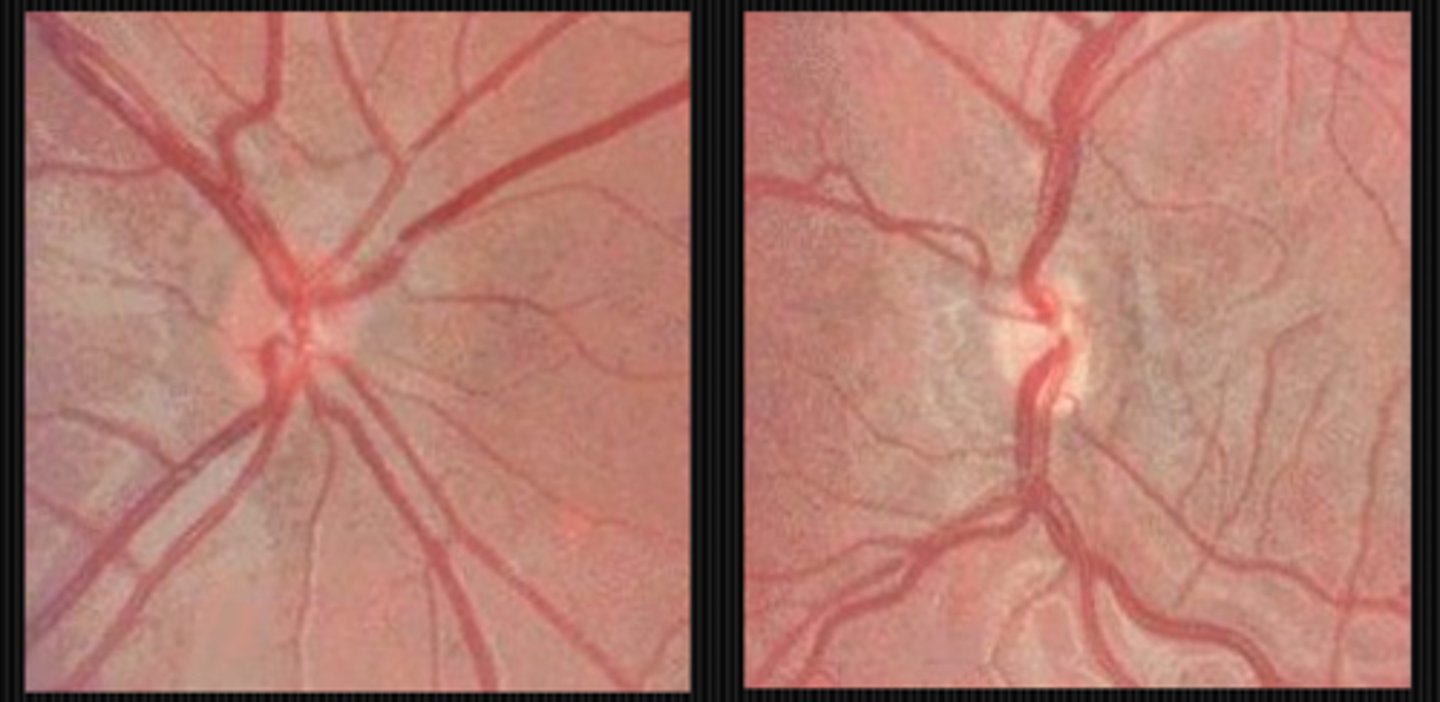

How can we differentiate papilledema from drusen based on the cup?

papilledema = present

drusen = absent

How can we differentiate papilledema from drusen based on the disc margins?

papilledema = blurred sup and inf

drusen = symmetric, scalloped blur

How can we differentiate papilledema from drusen based on the colour?

papilledema = hyperemic

drusen = normal

How can we differentiate papilledema from drusen based on the NRR?

papilledema = elevated rim that extends into RNFL

drusen = central elevation, bumpy

How can we differentiate papilledema from drusen based on the RNFL?

papilledema = edema sup and inf, muddy peripapillary reflex

drusen = focal atrophy, normal linear light reflexes

How can we differentiate papilledema from drusen based on the BV?

papilledema = optociliary shunts develop, venous dilation, absent SVP

drusen = central origin, trifurcation and other anomalous patterns, present SVP